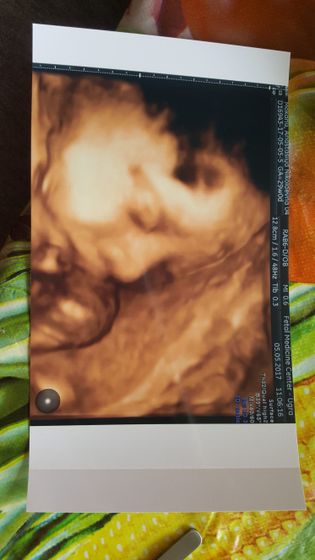

Девочки Сегодня самый лучший день, я хожу такая счастливая сходила вообщем я на платное узи, ибо 3 скрининг аж 28 числа. Наш вес 1700, мы опережаем все таки срок на две недели почти, тоесть по месячным 29 недель, по узи 30,5 д.

Имеем крупные щечки ??? и вообще сами по себе большие ибо должны весть 1200 где то.

Но это не страшно врач сказал так как на этом сроке это часто бывает. Лежим уже вниз головкой. Даже не верится что скоро я стану мамой этих сладких щечек???